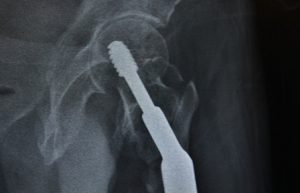

Añadió que aunque puede presentarse en cualquier hueso, la fractura de cadera es la más peligrosa, por ser altamente discapacitante e incluso puede llevar a la muerte, ya que cuatro de cada 10 personas que la sufren, no rebasan el siguiente año de vida a causa de diversas complicaciones como infecciones pulmonares, trombosis y formación de ulceras, por la poca o nula movilidad de quienes quedan postrados en una cama o limitados a una silla de ruedas.

Torres Martínez señaló que al año se presentan alrededor de 21 mil casos de fractura de cadera y que la importancia de atender esta enfermedad lo antes posible, radica en que la población mexicana tiende al envejecimiento.